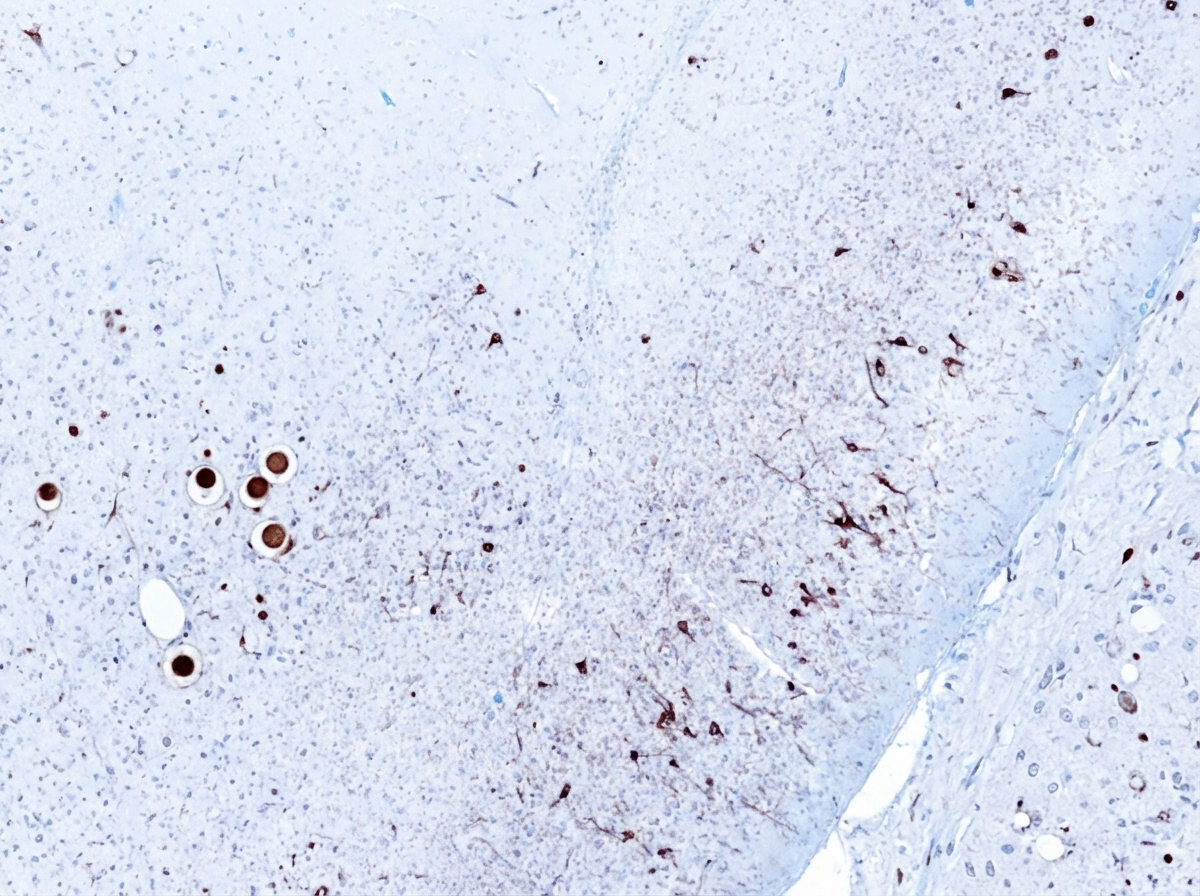

- Pathophysiology: Loss of dopaminergic neurons in substantia nigra pars compacta. Intraneuronal Lewy bodies (α-synuclein aggregates).

- Parkinson's disease features Lewy bodies (α-synuclein) and loss of dopaminergic neurons in the substantia nigra.